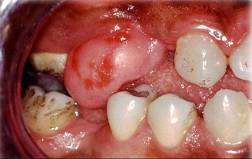

组图为口内纤维瘤的外观,关于此病的描述不正确的是 ( )

组图为口内纤维瘤的外观,关于此病的描述不正确的是 ( )![]()